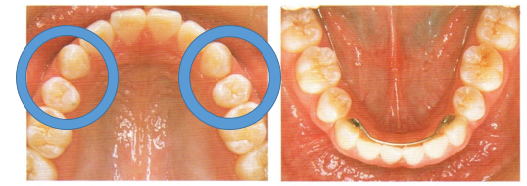

また、個性正常咬合の抜歯矯正を行うと、オーバートリートメントとなって下の写真の様に歯と歯の間に隙間が残っている場合があります。20世紀最高峰のアレキサンダー先生でもです。

歯・口腔の健康診断パネル③ 抜粋 アレクサンダーの矯正臨床p55抜粋

20世紀の最高峰の矯正医アレクサンダー先生が完全な個性正常咬合であると認めている

歯並びに対して口もとが前突気味だと言うだけで患者さんの主訴(同意)もかえりみず抜歯をすることが頭に浮かんでしまう矯正医が少なからずいます。

今回の症例は患者さんの強い主訴があるためにアレクサンダー先生は抜歯矯正処置を行いました。

歯・口腔の健康診断パネル③ 抜粋 アレクサンダーの矯正臨床p55抜粋